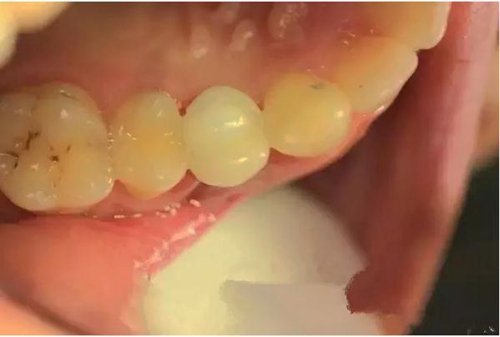

種植體長牢后,在種植體上安裝種植牙冠

種植牙修復后,種植體與牙槽骨緊密結合,種植牙與真牙外觀極其相似,上下牙咬合正常,種植體周邊無骨吸收情況。整個治療時長6個月,術后修復效果良好。

術后效果

從外觀上看根本分辨不出哪顆是種植牙,感受到跟真牙一樣的咀嚼力,口氣清新了,也變得更有自信了。